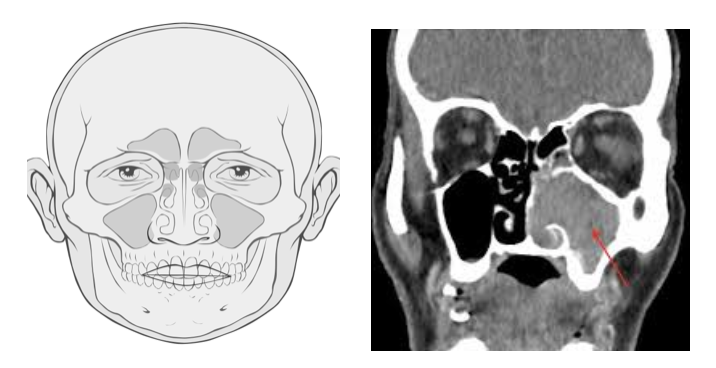

Первый шаг в диагностике подозрение. Если есть такие жалобы, как заложенность носа, носовое кровотечение и боль, которые не поддаются лечению, пациент должен быть готов к забаливанию рака. Необходимо выполнить полное ЛОР-исследование, кроме того, глаза и неврологические системы должны быть детально исследованы. То, что является первым выбором в качестве рентгенологической визуализации, является компьютерная томография. С помощью этого метода оценивается состояние костной структуры и оценивается, связано ли с опухолью. Мягкие ткани оцениваются с помощью МРТ, и разделение воспалительной ткани на опухоль выполняется более точно.Если во время эндоскопического или интраорального обследования обнаруженыподозрительные ткани, в этом случае следует провести биопсию. Радиологической процедуры взятия биопсии.Было бы более целесообразно выполнить процедуру биопсии после рентгенологических исследований. Поскольку опухолевая ткань обычно находится в закрытых полостях синуса, она не всегда может быть обнаружена при обследовании, и ее присутствие обнаруживается только по рентгенологическим изображениям. В таких случаях может потребоваться биопсия в условиях операционной.